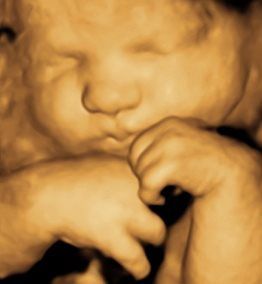

A Little Insight is proud to announce that we now offer 8K technology. This is the most realistic & amazing view of your unborn baby.

A Little Insight is an elective ultrasound center dedicated to providing a private experience that focuses on you and your baby, and we believe that every parent deserves to maximize their prenatal experience. Our 3D/4D & 5D ultrasounds provide an opportunity for you to see your baby not only in still image but in real-time motion. Why wait until your baby is born to celebrate his/her life?

A Little Insight 3D/4D/5D Ultrasound is unique because we truly offer the finest 3D/4D & 5D prenatal experience available. We combine cutting-edge technology with a family theater environment to bring you incredible images of your unborn baby in the womb. Best of all, we offer an unparalleled bonding experience that you and your family can cherish for a lifetime!